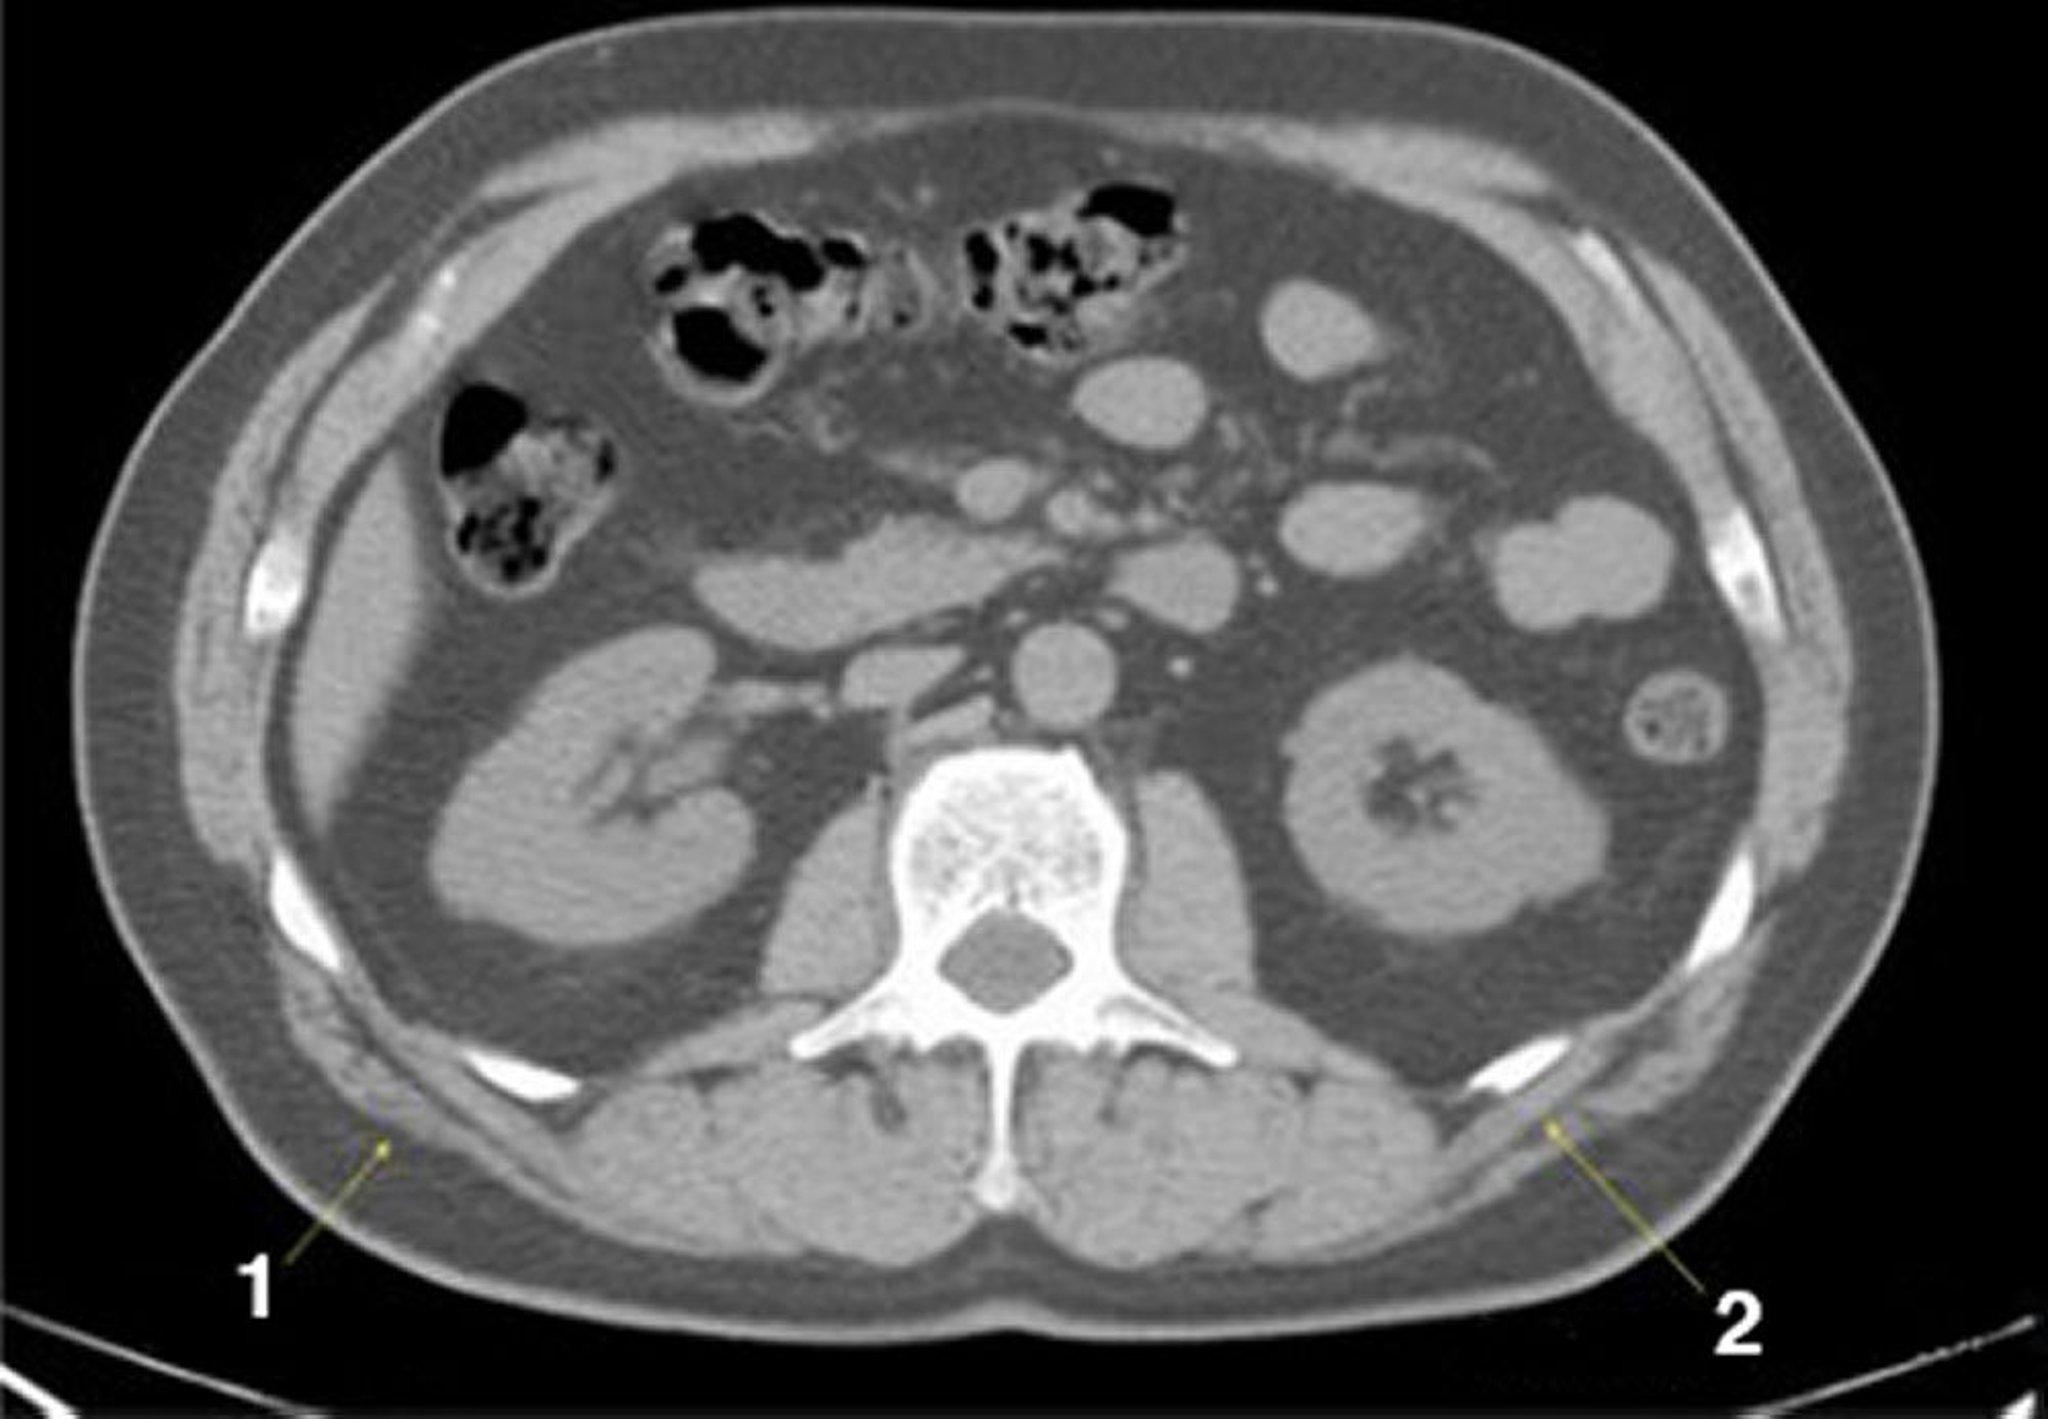

CT-Scan von Abdomen und Becken mit normaler Anatomie ohne Kontrastmittel (Folie 15)

1 = M. latissimus dorsi; 2 = M. serratus posterior.